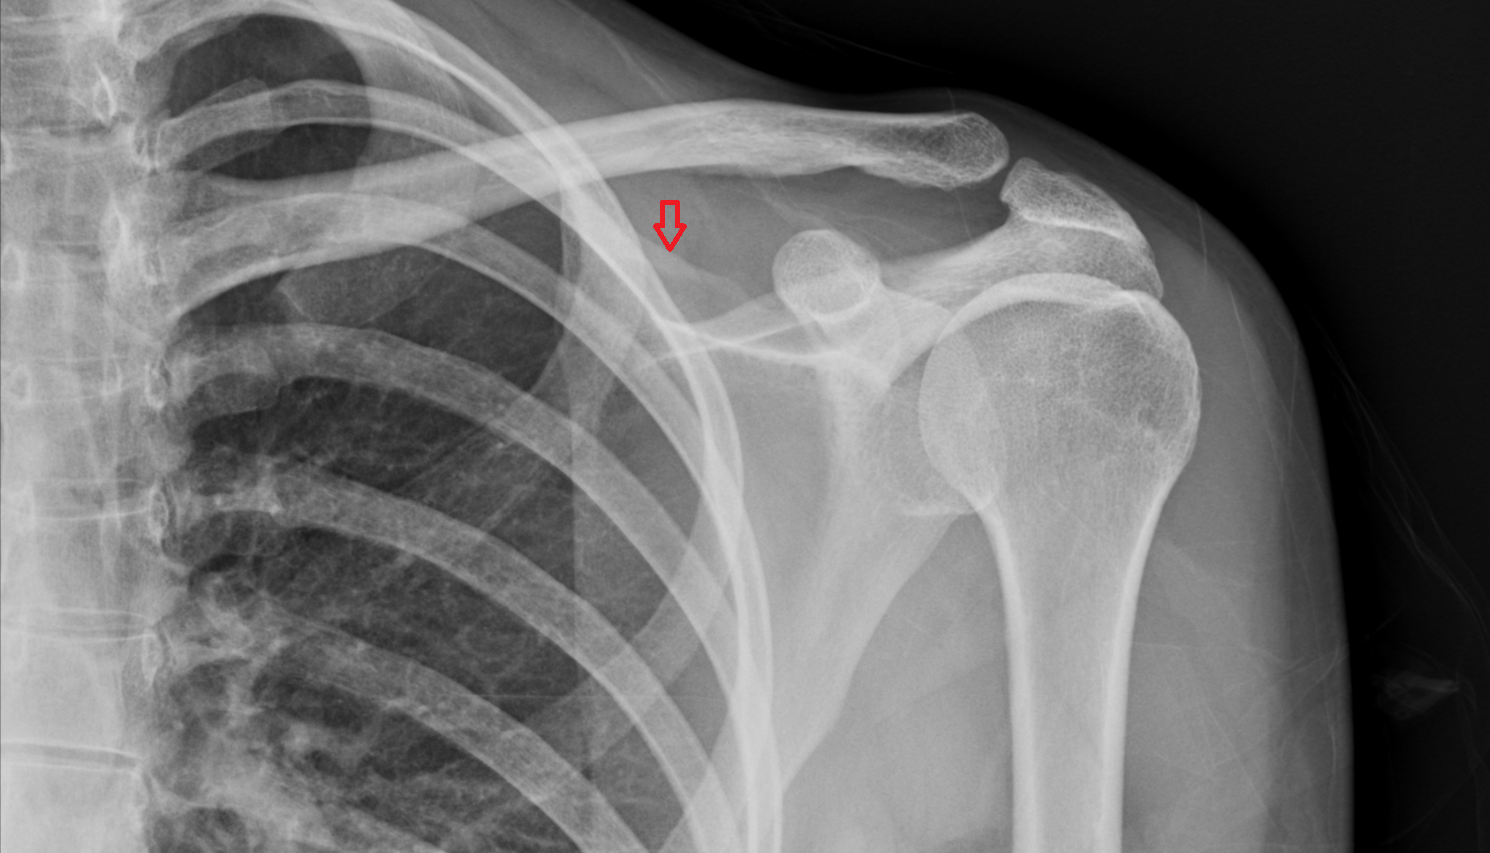

- Spine of scapula

- Acromion process of scapula

- Coracoid process of scapula

- Shaft (body) of clavicle

- Acromial end of clavicle